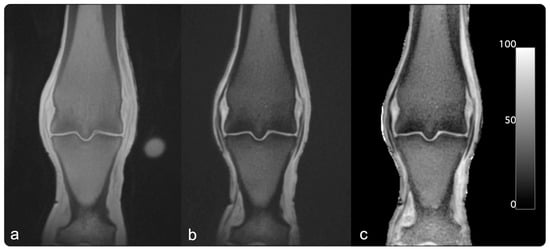

Figure 1.

Example MR images: UTE images were acquired using dual-echo UTE sequences. Image (a) was acquired with a short echo time of 0.04 ms (echo1). Image (b) was acquired with a longer echo time of 2.68 ms (echo2). For the PI image in panel (c), porosity index was calculated using the following formula: . For presentation in this figure, the background was manually set to zero.